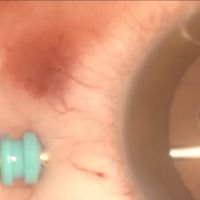

Complicaciones tardías de las ampollas filtrantes: Blebitis

Dr. Guido BlancoPaciente con trabeculectomia, ampolla filtrante, blebitis y endoftalmitis con vitrectomia de urgencia -